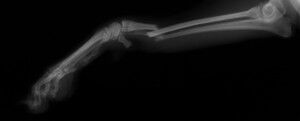

こんばんは、フジタどうぶつ病院です。今日はトイ・プードルの橈尺骨骨折の治療についてご報告させて頂きます。トイ・プードルは脚が長く、骨が細いので非常に骨折が多い犬種です。椅子やソファーから降りた時に折れたり、中には飼い主さんの後ろを歩いていて気づいたら脚を挙げていて病院でレントゲンを撮ったら折れていた、ということもあるようです。今回の症例報告のワンちゃんは椅子から降りた時に折れてしまったようです。下の写真が病院に来院時に撮ったレントゲン写真です。前脚の橈骨と尺骨が折れています。